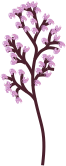

Der Stamm des Baums endet in der Brustwarze, seine Äste und Zweige entsprechen den Milchgängen, und die Blätter bilden die Milchdrüsenläppchen. Die 'Blätter' sind allerdings nicht flach, sondern sehen eher wie Himbeeren mit einem kurzen Stiel aus - hier eine Sicht durch das Mikroskop:

Der Stamm des Baums endet in der Brustwarze, seine Äste und Zweige entsprechen den Milchgängen, und die Blätter bilden die Milchdrüsenläppchen. Die 'Blätter' sind allerdings nicht flach, sondern sehen eher wie Himbeeren mit einem kurzen Stiel aus - hier eine Sicht durch das Mikroskop:

Mit freundlicher Genehmigung von Prof. László Tabár